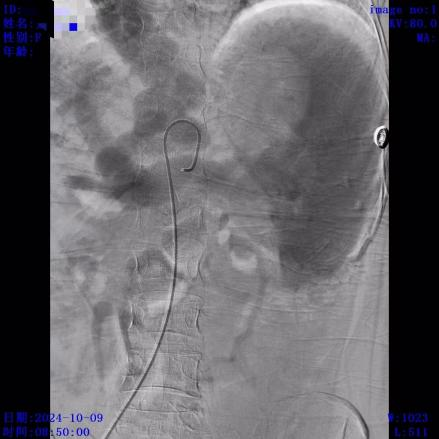

患者经内镜止血术后出血停止,返回病房继续对症治疗。术后复查患者血常规提示血红蛋白与术前相比有所回升,但血小板持续低下,最低达25(10^9/L),考虑与脾大、脾功能亢进(简称脾亢)有关。血小板是人体负责止血的血细胞,重度血小板低下会导致皮肤/牙龈出血、伤口渗血不止甚至严重内脏出血,严重影响生命健康,但脾亢常规药物保守治疗效果不明显,且血小板寿命短,输注血小板也仅仅能短期维持,非长久之计。结合临床,患者有行部分脾动脉栓塞术(PSE)以减轻脾亢指征。经患者及家属签字同意,10月9日由消化内科介入团队为患者施行经皮脾动脉部分栓塞术,过程顺利。术后经消化内科医护团队精心治疗,患者日前已顺利出院。出院后随访至今患者病情稳定,恢复良好,复查血常规提示血小板升至 72(10^9/L)。

脾栓塞前

脾栓塞后